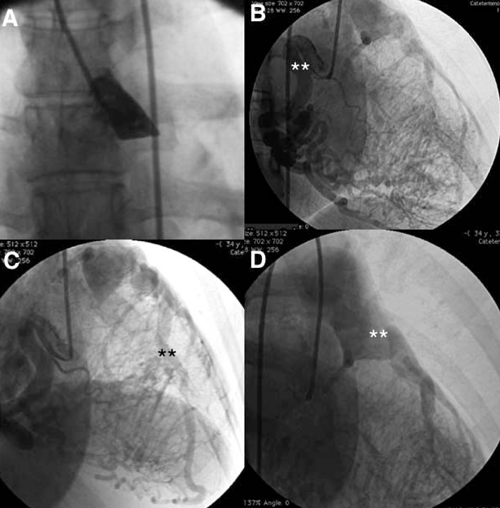

Con diagnóstico presuntivo de ALCAPA se realizó CACG que confirmó el nacimiento anómalo de la ACI desde la AP (figura 1).

Figura 1: Coronariografía. A) Ausencia de la arteria coronaria izquierda en el seno de Valsalva izquierdo. B) Arteria coronaria derecha dilatada, flexuosa (**), con importante red de colaterales septales. C) Arteria descendente anterior ectásica (**), que recibe flujo desde la arteria coronaria derecha. D) Nacimiento de la arteria coronaria izquierda desde la arteria pulmonar (**).